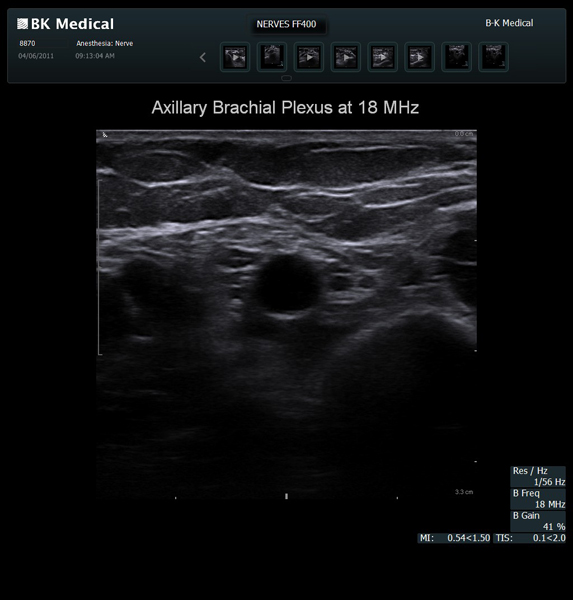

High resolution ultrasound imaging for needle-guided procedures.

The Flex Focus 400 exp ultrasound system offers premium image quality with fast frame rates for excellent temporal resolution. The system features Automatic Mode Adjustment (AMA) to optimize high resolution B-Mode Imaging when changing modes and depth.

Transducers Designed for Guidance

BK Medical offers high-frequency linear transducers, imaging from 18-2 MHz for upper and lower extremities, and curved array abdominal transducer 8820e for special deep nerves or paravertebral/spinal applications. Our transducers provide superb detail that makes it easy to see your needle during procedures.